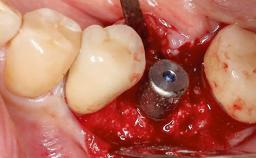

Due to their promising clinical performance, zirconia implants have recently become popular alternatives to titanium implants, particularly for areas with high esthetic demands (Holländer and coworkers 2016; Roehling and coworkers 2016; Lorenz and coworkers 2019). However, regardless of the reported high survival and success rates, zirconia implants were affected by peri-implant diseases over the short observation period, suggesting the importance of treating peri-implant diseases at zirconia implants (Becker and coworkers 2017). In their case, Frank Schwarz and Ausra Ramanauskaite present 3-year results following mechanical debridement alongside Er:YAG laser monotherapy.